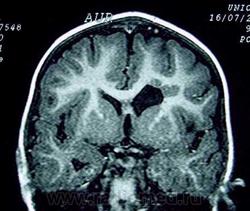

Гетеротопии. Перивентрикулярная гетеротопия. Субэпендимальная нодулярная (узелковая) гетеротопия.

Наиболее частым вариантом миграционных нарушений является гетеротопия - скопление нейронов, остановившихся в различных аномальных местах на пути следования к коре головного мозга. Такая остановка происходит не позже 5-го месяца внутриутробного развития. Изолированный участок узловатой массы называется «гетеротопион». В настоящее время описаны следующие варианты гетеротопии:

Перивентрикулярная субэпендимальная гетеротопия